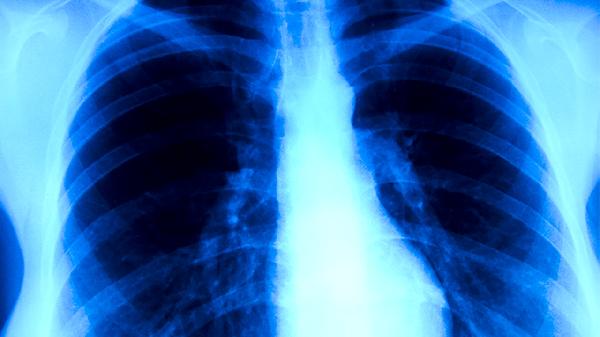

肺结核患者需遵医嘱使用异烟肼片、利福平胶囊、吡嗪酰胺片、乙胺丁醇片、链霉素注射液等抗结核药物联合治疗。肺结核是由结核分枝杆菌感染引起的慢性传染病,规范用药是治愈的关键。

肺结核患者应严格遵循早期、联合、适量、规律、全程的用药原则,完成6-9个月的标准疗程。治疗期间需保持高蛋白、高维生素饮食,适当补充牛奶、鸡蛋、瘦肉等优质蛋白,避免辛辣刺激性食物。注意休息并做好隔离防护,定期复查胸部影像学和痰菌检查,出现药物不良反应及时就医调整方案。保持居室通风良好,咳嗽时掩住口鼻,痰液需消毒处理。